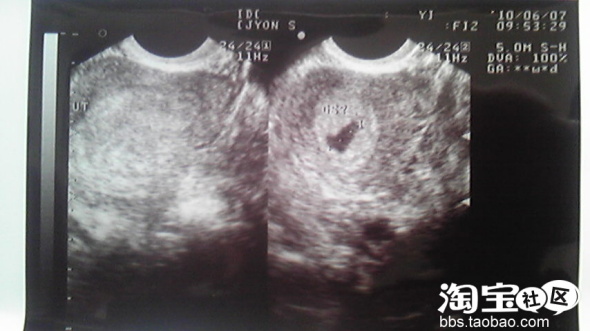

帮我看一下B超图,怀孕一个月,没照到胎囊

这是什么>?医生说可能是血块可能流产了,让我要是有流血块的东西下来的话带去检查....

我想知道如果没有怀孕B超是不是跟图片上的左边一样什么也没有的?医生给我看了正常的怀孕一个多月的B超图,子宫里应该是类似圆圆的胎囊...好怕,我现在还没流血也不肚子痛,怎么办.....是B超好不确定吗?那,,那块黑影是什么呢?

楼主,要不你先等几天看看,我以前也有跟你差不多的类型,都一个月了,B超也看不出怀孕,但血验出来是怀孕了,最后查来查去的,又说我掉了!唉!真不知道一开始到底有没有怀孕

一个月本来也照不出什么吧,时间太短了,说不定是刚怀上,再等几天看看。

楼主没有验血吗?一般要50天左右才能超出的。才一个月太早了吧,别自己吓自己啊亲不必太担心,医生也说了流血再去检查呢。太紧张了对宝宝也不好。我也是刚刚验血知道有了宝宝的,,,医生说要过两三个星期后再去照B超,,,希望一切顺利吧